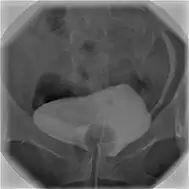

Cystographie

La cystographie est une radiographie qui permet d'explorer les parois de la vessie et de l'urètre. Cet examen utilise des rayons X et un produit à base d'iode. Ce dernier est le plus souvent injecté directement dans la vessie à l'aide d'une sonde passant par l'urèthre (cystographie rétrograde), plus rarement en piquant dans la vessie à travers la paroi abdominale (cystographie suspubienne)[1].

Les clichés sont réalisés en deux temps. D'abord pendant le remplissage de la vessie, puis dans un second temps, pour étudier les parois de l'urèthre, des clichés seront pris pendant que le patient urine[1]. La cystographie est complémentaire de l'échographie permettant de voir des anomalies qui échappent à cette dernière[3],[4]. On appelle cystogramme les images obtenues avec la cystographie.